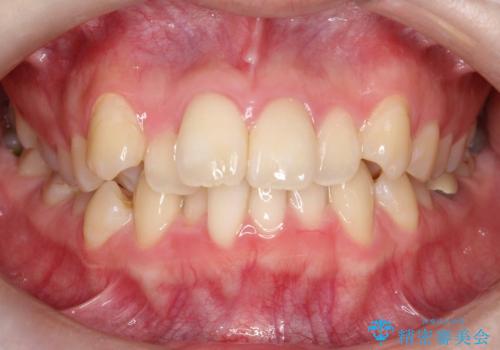

[セラミック治療] 前歯の審美治療に伴う矯正治療